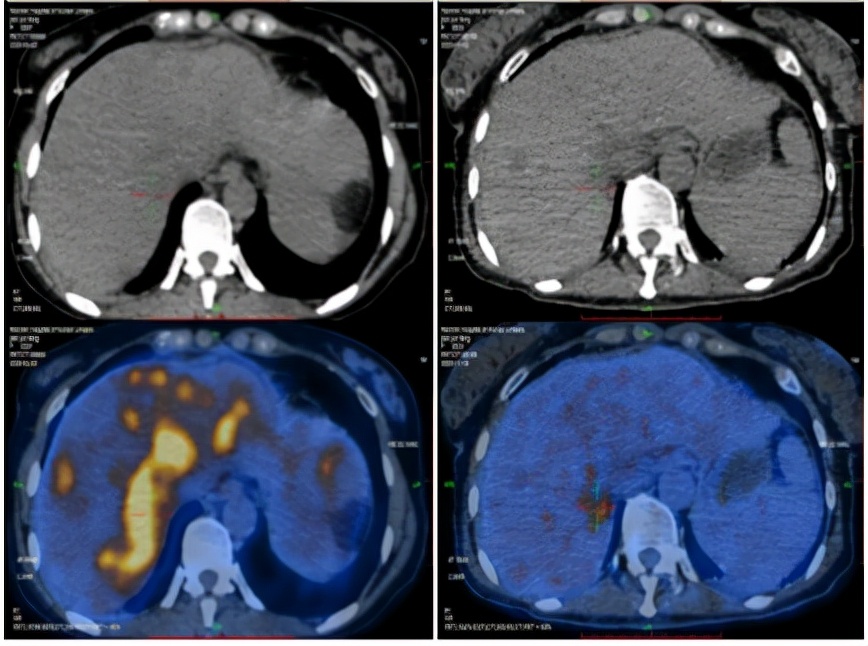

2020-11-18PET-CT提示:1.胰腺体部结节,代谢增高;肝实质多发稍低密度团块、结节灶,代谢增高;全身多发骨质密度不均,代谢稍增高;上述考虑胰腺癌伴多发转移灶治疗后改变,少许活性尚存。2.左锁骨上区及胸廊入口处淋巴结,较前缩小,代谢减低;肝门区、胰腺周围及腹膜后区高代谢淋巴结未见明显显示;上述考虑转移灶经治疗后改变,活性受抑

2020-4-22 2020-11-18